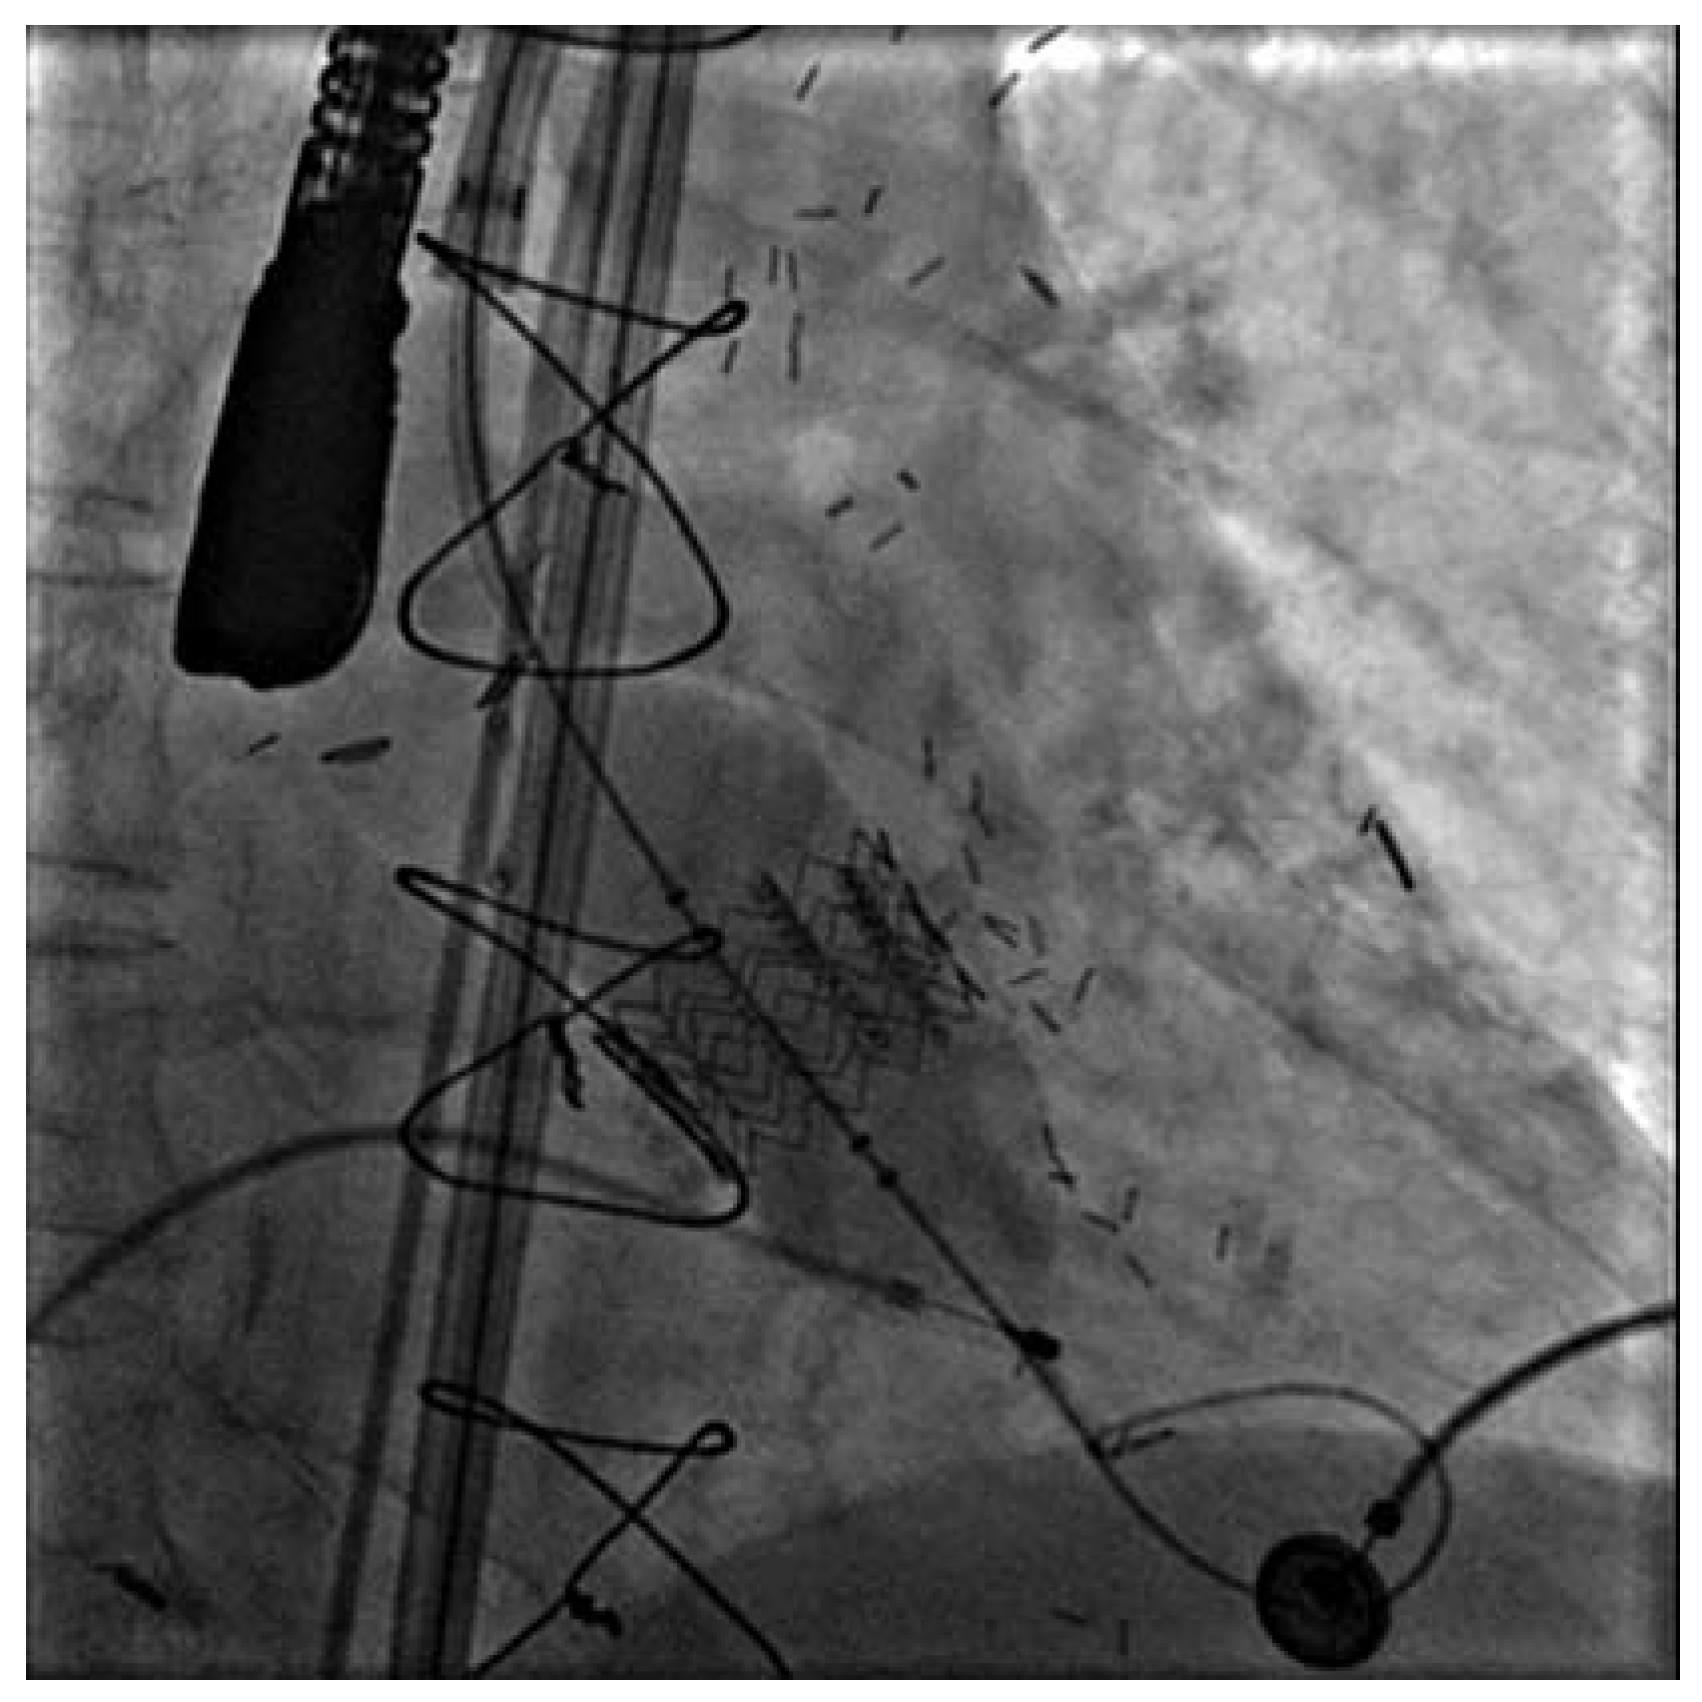

Bei all diesen Erfolgen und der Bedeutung der koronaren Herzkrankheit sollten andere, weniger häufige, jedoch klinisch bedeutsame Krankheitsbilder aus der kardiovaskulären Medizin nicht vergessen werden. So sind auch die Klappenleiden, vor allem im Bereich der Mitral- und Aortenklappe, für viele Patientinnen und Patienten symptomatisch und bezüglich der Prognose bedeutsam. Mit der Überalterung der westlichen Gesellschaften hat vor allem die degenerative Aortenstenose heute eine enorme Bedeutung erlangt. Sie tritt vornehmlich in der ältesten Altersgruppe auf, insbesondere bei 70- bis über 80jährigen Patientinnen und Patienten. Das Leiden beeinträchtigt die Lebensqualität der Betroffenen erheblich und führt zu Atemnot, Angina pectoris, Schwindel, zerebrovasklulären Embolien und zum plötzlichen Herztod. Durch die Einführung der Echokardiographie wurde die Diagnose und Gradierung dieses Klappenleidens auf einfache und überall verfügbare Weise möglich. Die Entwicklung mechanischer und biologischer Klappen für herzchirurgische Eingriffe hat zudem die operative Behandlung dieser Erkrankungen stark verbessert. Heute lässt sich ein Aortenklappenersatz auch bei älteren Patientinnen und Patienten über 80 Jahre mit einer geringen Mortalität und Morbidität durchführen. Dennoch ist für viele, besonders polymorbide Patientinnen und Patienten dieser Eingriff immer noch mit einem erheblichen Risiko verbunden. Entsprechend hat sich die interventionelle Forschung der letzten zehn Jahre darum bemüht, perkutane implantierbare Aortenklappen verfügbar zu machen (

Figure 1). Obschon der Eingriff immer noch nur im Rahmen von Protokollen und bei Hochrisikopatienten, welche durch Herzchirurgen abgelehnt werden, in Betracht gezogen wird, hat die Technik wie auch das verfügbare Material enorme Fortschritte gemacht. Heute sind verschiedene Klappen verfügbar, welche mit immer noch grossen Schleussen femoral retrograd über die Aorta eingeführt und in der Aortenwurzel mit einem Ballon implantiert werden können. Die Resultate der ersten kleinen Serien sind ermutigend und es ist absehbar, dass der perkutane Aortenklappenersatz zumindest bei chirurgischen Hochrisikopatienten in mittelbarer Zukunft routinemässig verfügbar wird.

Bei all diesen Erfolgen und der Bedeutung der koronaren Herzkrankheit sollten andere, weniger häufige, jedoch klinisch bedeutsame Krankheitsbilder aus der kardiovaskulären Medizin nicht vergessen werden. So sind auch die Klappenleiden, vor allem im Bereich der Mitral- und Aortenklappe, für viele Patientinnen und Patienten symptomatisch und bezüglich der Prognose bedeutsam. Mit der Überalterung der westlichen Gesellschaften hat vor allem die degenerative Aortenstenose heute eine enorme Bedeutung erlangt. Sie tritt vornehmlich in der ältesten Altersgruppe auf, insbesondere bei 70-bis über 80jährigen Patientinnen und Patienten. Das Leiden beeinträchtigt die Lebensqualität der Betroffenen erheblich und führt zu Atemnot, Angina pectoris, Schwindel, zerebrovasklulären Embolien und zum plötzlichen Herztod. Durch die Einführung der Echokardiographie wurde die Diagnose und Gradierung dieses Klappenleidens auf einfache und überall verfügbare Weise möglich. Die Entwicklung mechanischer und biologischer Klappen für herzchirurgische Eingriffe hat zudem die operative Behandlung dieser Erkrankungen stark verbessert. Heute lässt sich ein Aortenklappenersatz auch bei älteren Patientinnen und Patienten über 80 Jahre mit einer geringen Mortalität und Morbidität durchführen. Dennoch ist für viele, besonders polymorbide Patientinnen und Patienten dieser Eingriff immer noch mit einem erheblichen Risiko verbunden. Entsprechend hat sich die interventionelle Forschung der letzten zehn Jahre darum bemüht, perkutane implantierbare Aortenklappen verfügbar zu machen (

Figure 1). Obschon der Eingriff immer noch nur im Rahmen von Protokollen und bei Hochrisikopatienten, welche durch Herzchirurgen abgelehnt werden, in Betracht gezogen wird, hat die Technik wie auch das verfügbare Material enorme Fortschritte gemacht. Heute sind verschiedene Klappen verfügbar, welche mit immer noch grossen Schleussen femoral retrograd über die Aorta eingeführt und in der Aortenwurzel mit einem Ballon implantiert werden können. Die Resultate der ersten kleinen Serien sind ermutigend und es ist absehbar, dass der perkutane Aortenklappenersatz zumindest bei chirurgischen Hochrisikopatienten in mittelbarer Zukunft routinemässig verfügbar wird.